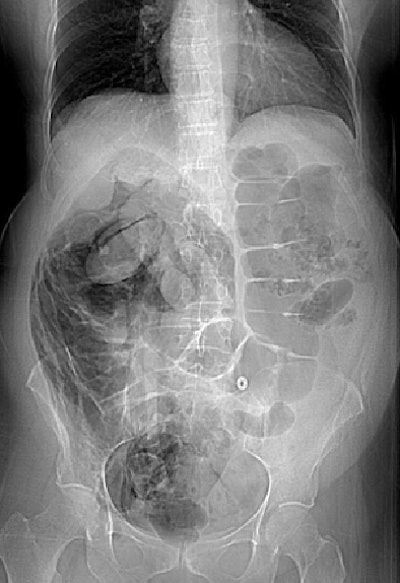

The second patient with perforation was a 70-year-old woman who had undergone screening colonoscopy. Acute angulation of the sigmoid colon prevented the colonoscope from being advanced more than 25 cm, and after five minutes of unsuccessful maneuvering it was removed. The patient had mild tenderness of the abdomen but no peritonism. She was admitted overnight and treated with antibiotics and IV fluids.

Overnight she developed worsening pain and a 38° C fever. "A diatrizoate meglumine and diatrizoate sodium solution enema examination the following morning showed no evidence of leak," they wrote. Symptoms resolved within 48 hours, and the patient was discharged from the hospital three days later with no further complications.

| Seventy-year-old woman who has undergone incomplete colonoscopy. Above and below: Axial CT scans of abdomen obtained before CT colonography show extensive retroperitoneal gas secondary to colonic perforation. Bottom image: Scout view from same examination shows extensive retroperitoneal air. All images courtesy of the American Roentgen Ray Society. Source: Hough DM, Kuntz MA, Fidler JL, et al. Detection of occult colonic perforation before CT colonography after incomplete colonoscopy: perforation rate and use of a low-dose diagnostic scan before CO2 insufflation. AJR. 2008;191:1077-1081. |